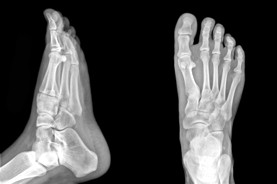

Alberta Foot Doctor & Foot Physio Therapist

The Foot Institute is an association of Alberta Doctors specializing in the medical treatment of the foot and ankle, and is one of the largest groups of foot specialists in Alberta.

The Alberta Foot Institute is dedicated to the medical and surgical treatment of the foot. Our mandate is to provide the best possible medical, surgical and preventative treatment available for our patients. We do this by providing well-trained Doctors who are committed to treat and prevent all types of foot pain, biomechanical disorders, as well as all other problems relating to the feet.

At the Alberta Foot Institute, our Doctors are trained to specifically treat problems associated with your feet or ankles. Below are several of the most common problems that we see on a day to day basis: